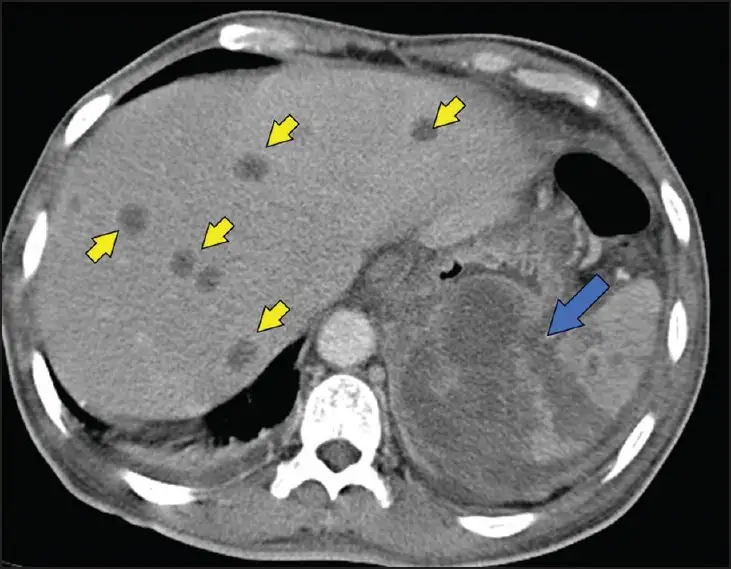

另一种可能性是,细菌在某些器官中形成了微小的脓肿——小到难以被检测,却又大到足以容纳一个休眠的细菌群落。这些脓肿可能位于前列腺、脾脏或肝脏深处,在数十年间不引起任何症状。然而,当条件合适时,脓肿破裂,细菌释放,一场致命的感染便开始了。

脾脏是另一个常见的目标。在类鼻疽患者中,脾脏脓肿的发生率远高于其他细菌感染。CT扫描常常显示多个小而离散的低密度病灶,这种表现被称为"靶征"。然而,如果没有考虑到类鼻疽的可能性,医生们可能会将这种表现误认为淋巴瘤或转移性肿瘤。